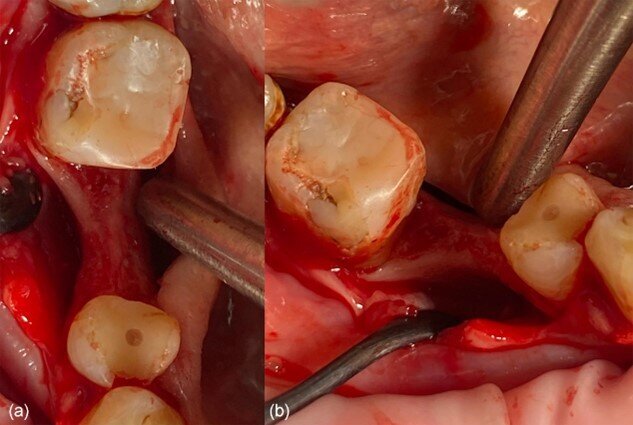

Fig. 6_a) Deiscenza vestibolare dopo la perforazione, b) situazione clinica dopo il posizionamento dell’impianto.

Fig. 7_Moncone di connessione in situ: a) vista occlusale, b) vista vestibolare.